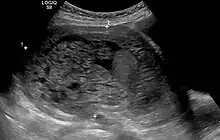

Transvaginal ultrasonography showing a molar pregnancy. -

Molar pregnancy in ultrasound -